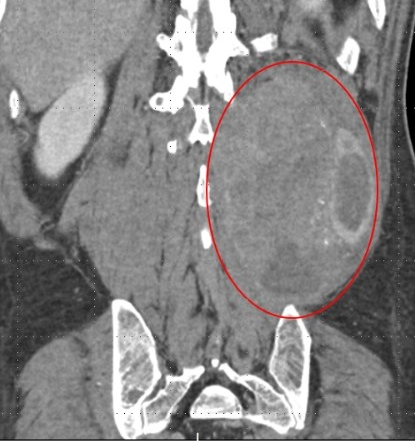

54岁的金先生是浙江台州人 在当地一家工厂上班 两年前,金先生为了改善生活 按揭买了套新房 自此以后每个月背上了房贷 他工作比以前更努力了 加班熬夜是家常便饭 从去年年初开始,金先生时常感觉到腰酸背痛,一开始以为只是上班坐久了,腰肌劳损导致的。直到半年前,他无意中摸到左侧后腰有个肿块,起初还以为是皮下囊肿,可能过几天自己就消下去了。 过了段时间,金先生心中感到不安,他腰痛越来越明显,而且肿块摸上去好像又变大了一点,于是抽空去当地医院就诊。检查后发现,他腰部的肿块大小竟然有10×15厘米,呈纺锤形,如同哈密瓜大小。 病理穿刺检查结果显示为平滑肌肉瘤,这是一种比较罕见的恶性肿瘤,起源于平滑肌细胞,常见于女性子宫、胃肠道、血管壁等部位,但也可能长到身体其他部位。 从影像上看,巨大肿瘤已经侵犯腰椎,而且紧紧贴着腰椎附近的神经和血管。手术难度非常大,当地医院建议金先生赶紧到上级医院治疗。 金先生来到浙江大学医学院附属第二医院骨科,医生介绍,金先生的肿瘤长在左后腰的肌肉里,位置比较深,不易被察觉。等到出现腰痛症状,徒手可以摸出肿块时,肿瘤已经非常大了,还侵犯了腰椎,情况比较复杂。 随后,院方召集了骨科、肿瘤内科、血管外科等多学科专家会诊,制定了详细的治疗方案:平滑肌肉瘤对化疗中度敏感,可以先进行术前的新辅助化疗,尽可能缩小肿瘤范围后,再进行手术切除。 从去年11月底开始,金先生前期做了2次新辅助化疗,一个多月后,肿瘤缩小了一些,为手术切除肿瘤创造了更好的条件。 金先生的手术定在1月14日。为了提高手术安全性,术前,血管外科团队为金先生进行了“腰动脉栓塞术”,以减少术中的出血量。 医生介绍,由于肿瘤巨大,已经侵犯了腰椎,而且紧贴着肠道、肾脏等脏器,附近又分布着下腔静脉、腹主动脉等重要血管和神经,手术时必须非常小心,避免损伤脊髓和重要的血管神经及周围脏器。 先从腹部入路,仔细地把肿瘤分离开来,再从后腰入路,将整个肿瘤“连根拔起”。为了完整切除肿瘤,术中还切除了腰椎1、2、3节的一半椎体。完整切除巨大肿瘤后,金先生的左侧后腰几乎被“掏空”,失去肌肉和软组织的保护,对后续康复会造成影响。 为此,医生用“移花接木”的方法,在保留血供的前提下,将患者右侧背阔肌翻转覆盖到左后腰处,刚好填补了手术留下的缺口,对手术部位起到了很好的保护。 整个手术持续了7个多小时,非常成功。术后一周,金先生就可以下地了。目前,金先生已经出院,进行术后的巩固化疗,以减少复发风险。 医生提醒,平滑肌肉瘤的恶性程度较高,具有侵袭性和转移性,且生长速度较快,可通过血液或淋巴系统扩散到其他器官。早期可能无明显症状,但随着肿瘤增大,可能出现局部肿块、疼痛或压迫周围组织引起相关症状。 因此,如果摸到身上有不明肿块,大家千万不要掉以轻心,应及时到医院进行排查。